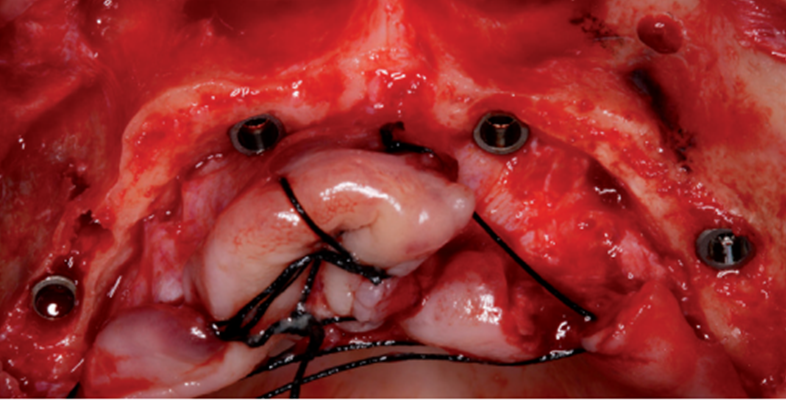

No mesmo momento foram instalados pilares Micro-Unit de 0º, 17º ou 30º (Implacil De Bortoli / São Paulo / Brasil) com 20 Ncm, corrigindo a inclinação dos implantes com o objetivo de facilitar a inserção da infraestrutura protética e conseguir a adaptação passiva.

As próteses foram confeccionadas com dentes e gengivas artificiais em acrílico, com infraestrutura metálica ou com barra pré-fabricada de fibra de vidro (De Fama Porto Alegre / Rio Grande do Sul / Brasil), conforme figura 3. As próteses foram instaladas com torque de 10 Ncm e os ajustes oclusais necessários foram realizados.